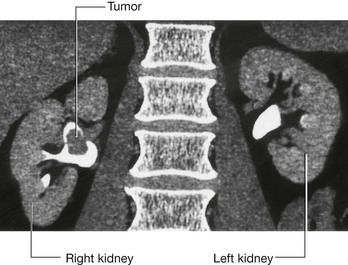

Page 392

Blood from the lower limbs and the pelvis may drain via a series of collateral vessels, some of which include the superficial inferior epigastric veins, which run in the superficial fascia. These anastomose with the superior, superficial, and deep epigastric venous systems to drain into the internal thoracic veins, which in turn drain into the brachiocephalic veins and the superior vena cava.

After the initial inferior vena cava thrombosis, the veins of the anterior abdominal wall and other collateral pathways hypertrophy to accommodate the increase in blood flow.

Case 3 LIVER BIOPSY IN PATIENTS WITH SUSPECTED LIVER CIRRHOSIS